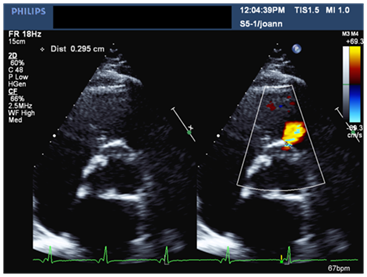

A 56-year-old male patient with long standing history of essential hypertension on treatment. Sustained type A aortic dissection with severe Aortic regugitation requiring urgent surgery. He had type A aortic dissection repair. He also received a mechanical aortic valve prosthesis three months prior to presentation to our institute. He was requring follow up. He denied symptoms of chest pain, shortness of breath or palpitations. His medical therapy consisted of Asprin, Lisinopril, Atorvastatin, Metopralol and Warfarin. His biochemical profile revealed a controlled LDL cholestrol. His blood pressure and heart rate were well controlled. An ejection systolic murmur and click were auscultated over the aortic area. Electrocardiogram showed sinus rhythm and left ventricular hypertrophy. A transthoracic echocardiogram showed normal biventricular size and systolic function, well-seated mechanical aortic prosthesis with acceptable hemodynamics. An abnormal systolic flow was noted by color Doppler at the right coronary sinus directed towards the right ventricular out flow tract (Figure 1 & 2). A transesophageal echocardiogram (TEE) demonstrated a well-seated aortic prosthesis with physiological trivial intra-valvular regurgitation and a small defect measuring four millimeters between the aorta and the right ventricle with abnormal systolic flow demonstrated at the right coronary sinus directed to the right ventricular outflow tract in keeping with aorto-right ventricular (ARV) fistula (Figure 3). No echocardiographic evidence of endocarditis is seen.

Figure 1 Parasternal long axis view in TTE showing mechanical aortic prosthesis with color flow doppler in systole indicating communication between the right coronary sinus and right ventricular outflow tract (RVOT).

Figure 2 Parasternal short axis view at the level of the aorta in TTE demonstrating flow to the RVOT with a measured neck of ~0.3cm.